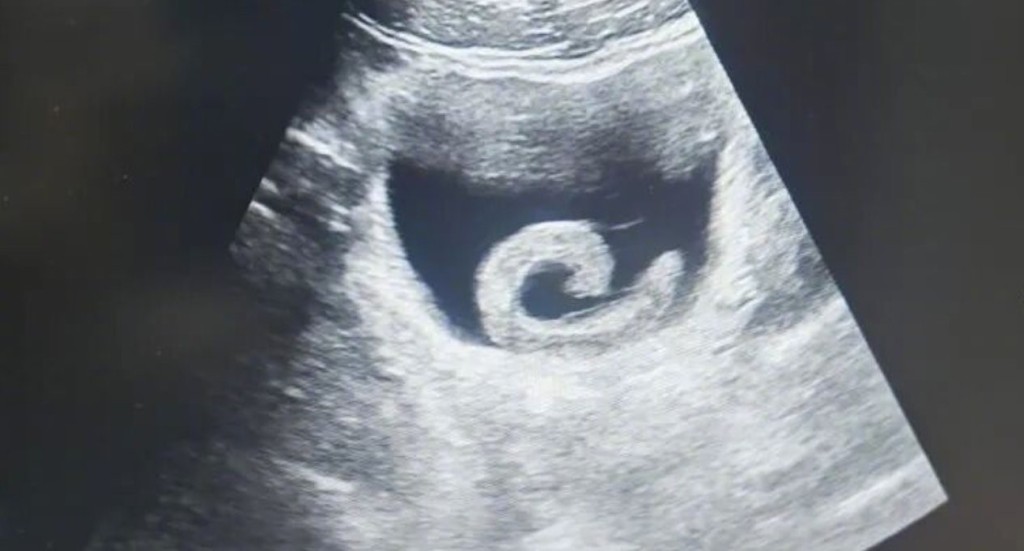

据报道,当时男子脸色苍白、满头冷汗抵达医院急症室,他佝偻著身体,双手紧捂下腹,面上因剧痛和恐惧而扭曲。医生即时替他进行超声波检查,结果发现男子膀胱内有正在蠕动的条状异物,周围还有出血现象。

超声波检查下,水蛭被发现在病人膀胱内寄居。《大河报》

泌尿外科副主任医生透过内窥镜检查,赫然发现膀胱内有一条长约5至6厘米的水蛭,吸吸付在膀胱黏上,更出现严重充血水肿,因而让男子剧痛和无法小便。